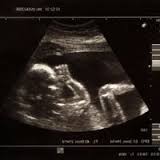

Le gynécologue qui prend en charge la grossesse et l’accouchement est un obstétricien, que l’on appelle aussi un accoucheur. Il suit la grossesse de ses patientes, et réalise les trois échographies habituelles en cours de grossesse.![]()